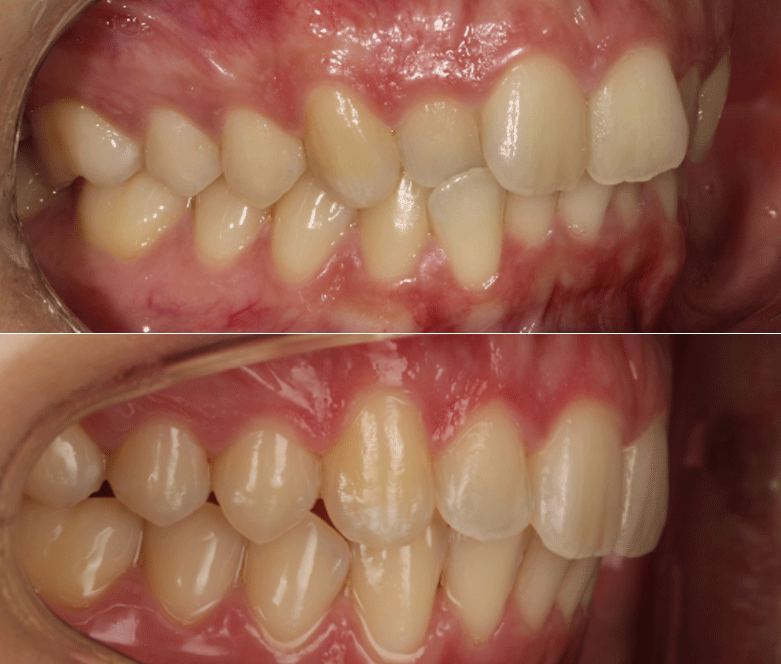

We will then map out a complete treatment plan showing the gradual realignment that will reposition the teeth from their current position to where they will be when the treatment is complete.